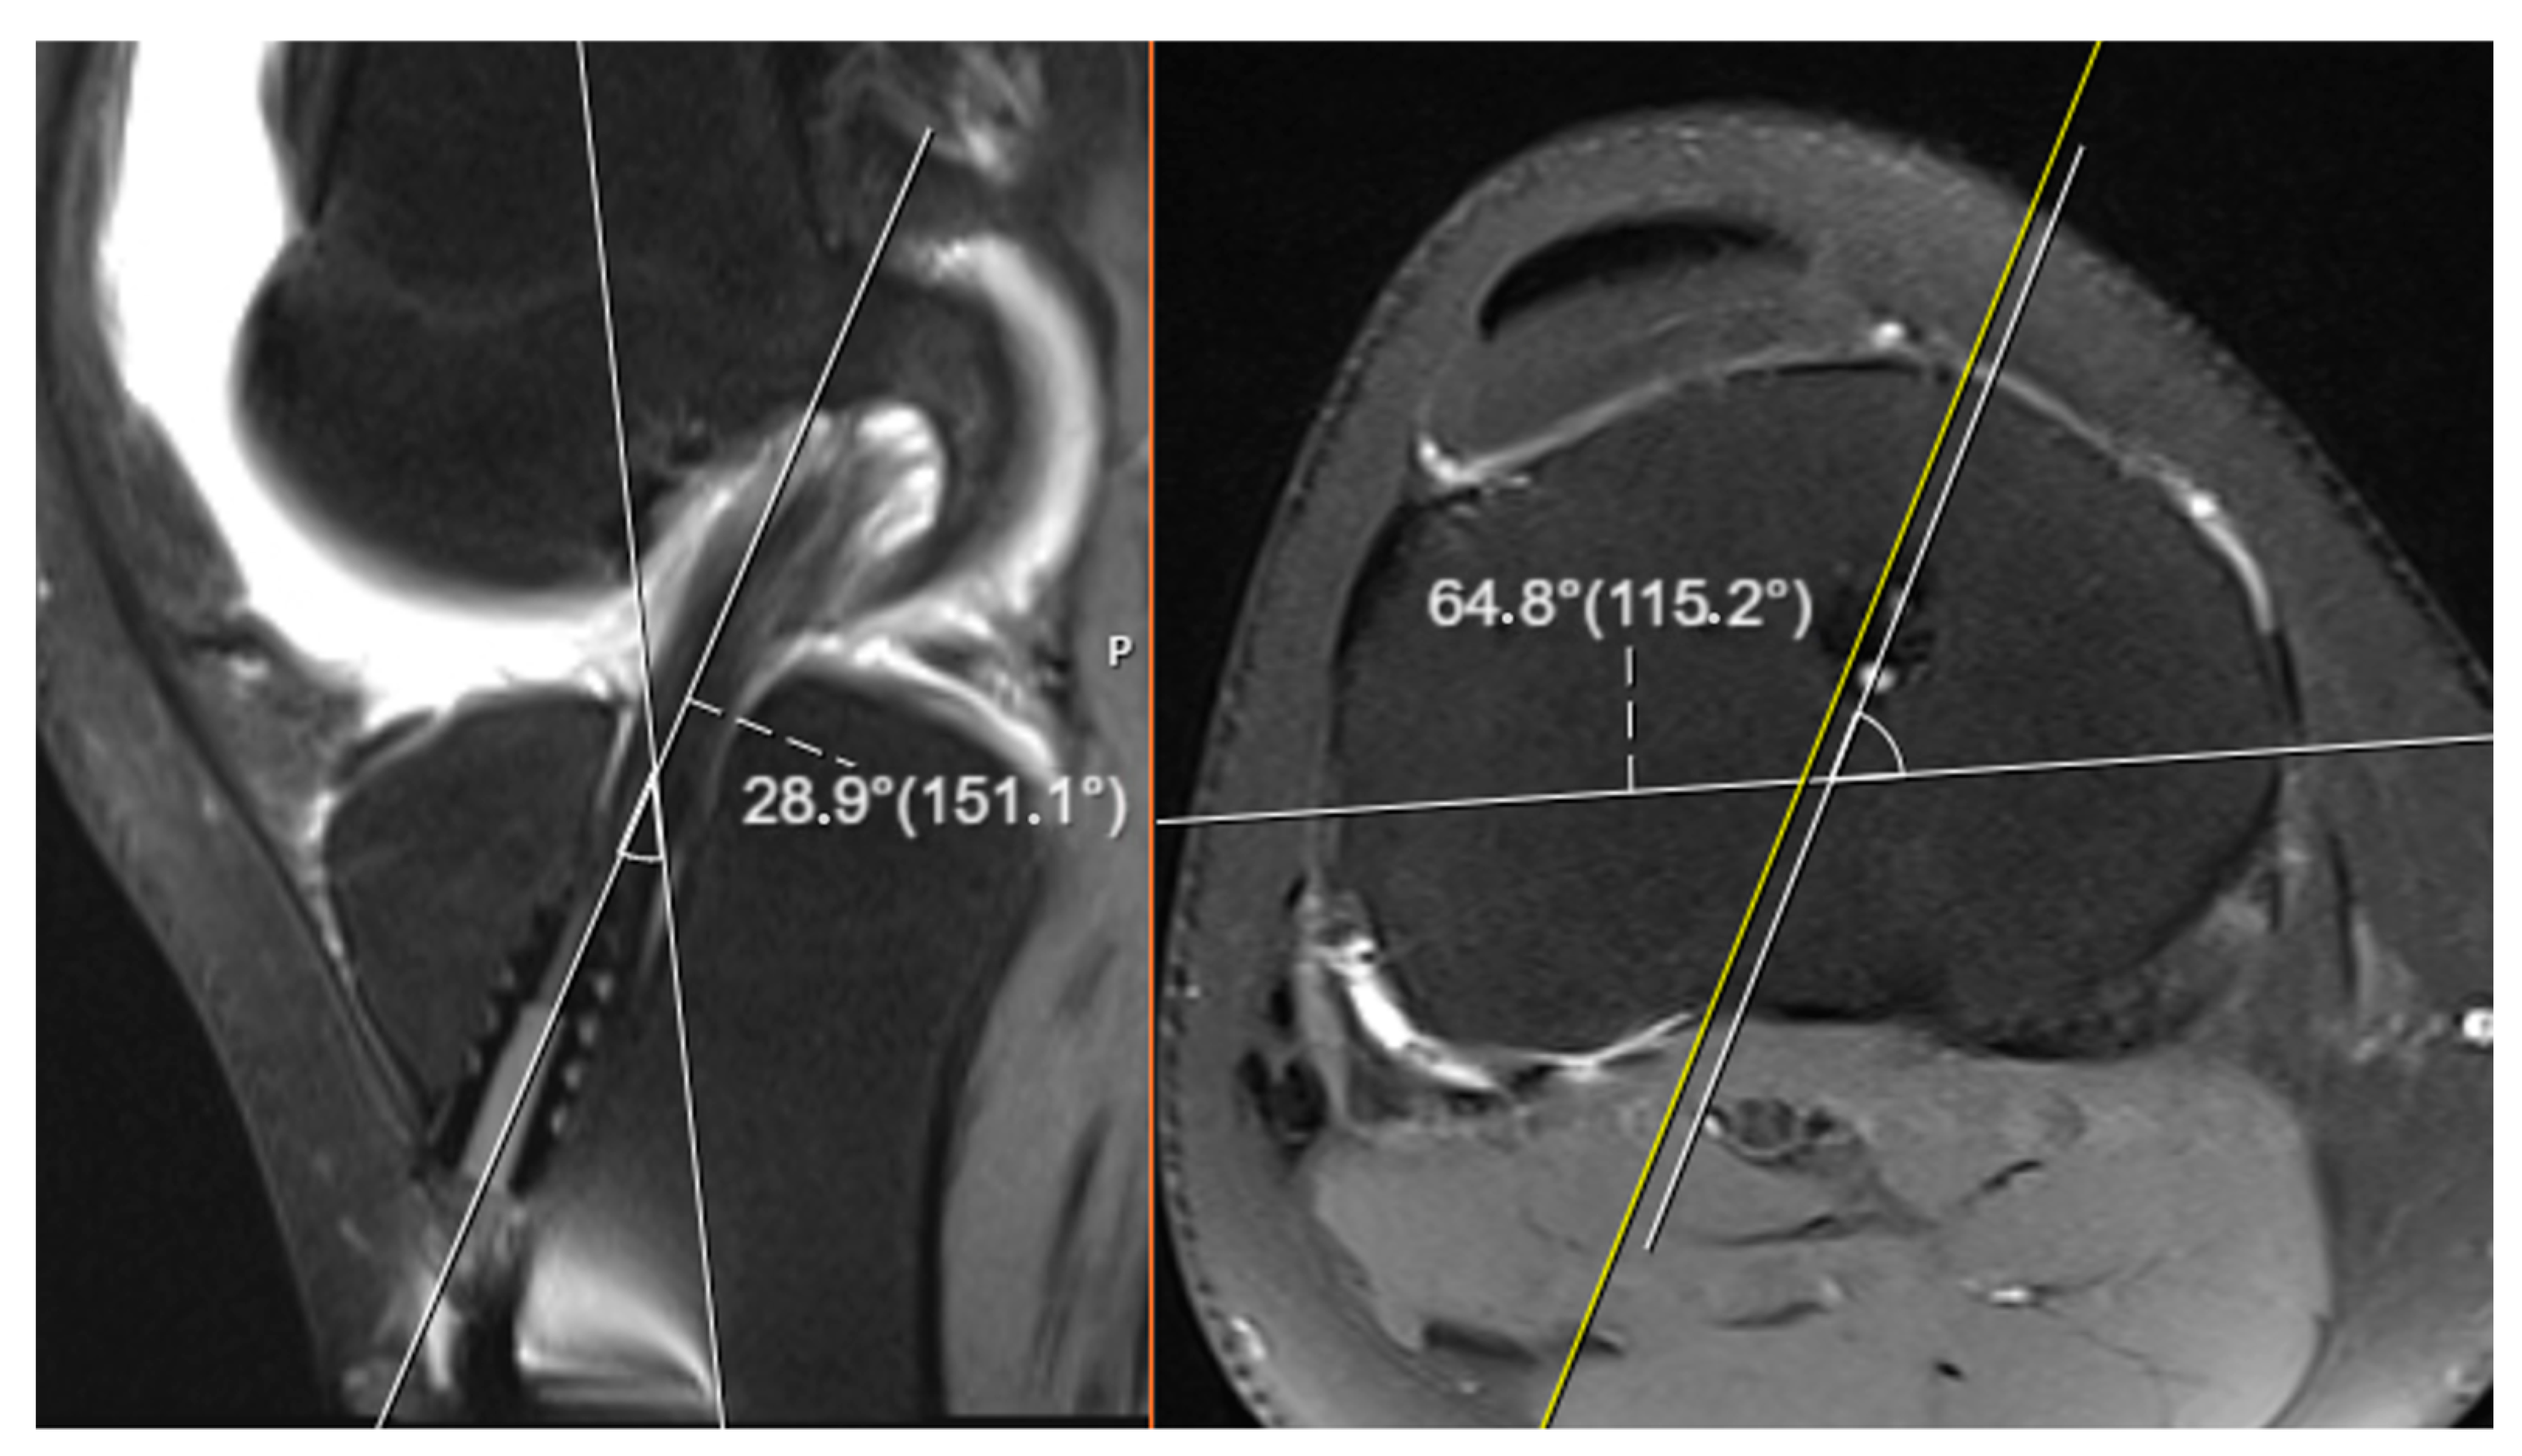

The tibial tunnel angles derived through these three-dimensional calculations obtained solely from conventional roentgenographic images were subsequently compared with the actual tunnel angles measured directly on magnetic resonance imaging (MRI) scans. This comparison was performed to evaluate the degree of correlation, the extent of deviation, and the overall accuracy between the two distinct measurement approaches (see Figure 3). In the context of this study, the tunnel angles computed from roentgenograms were denoted by the symbols α and β, whereas the corresponding angles measured on MRI images were labeled as α′ (alpha prime) and β′ (beta prime), respectively. This symbolic differentiation was used throughout the analysis to clearly distinguish between values obtained by calculation and those determined via imaging.

For the MRI-based evaluations, oblique slices oriented parallel to the axis of the tibial tunnel were utilized in order to achieve accurate three-dimensional representations. These specific oblique images were carefully selected to align with the true orientation of the tunnel, allowing for more reliable angle measurement. In each case, two principal angular relationships were assessed: the angle formed between the tibial tunnel and the sagittal axis of the knee joint, and the angle formed between the tunnel and the anatomical longitudinal axis of the tibia. These MRI-based angle measurements served as the reference standard for assessing the validity and precision of the radiograph-based three-dimensional calculations.

Figure 3. Image showing the measurement of tunnel angles on MRI.